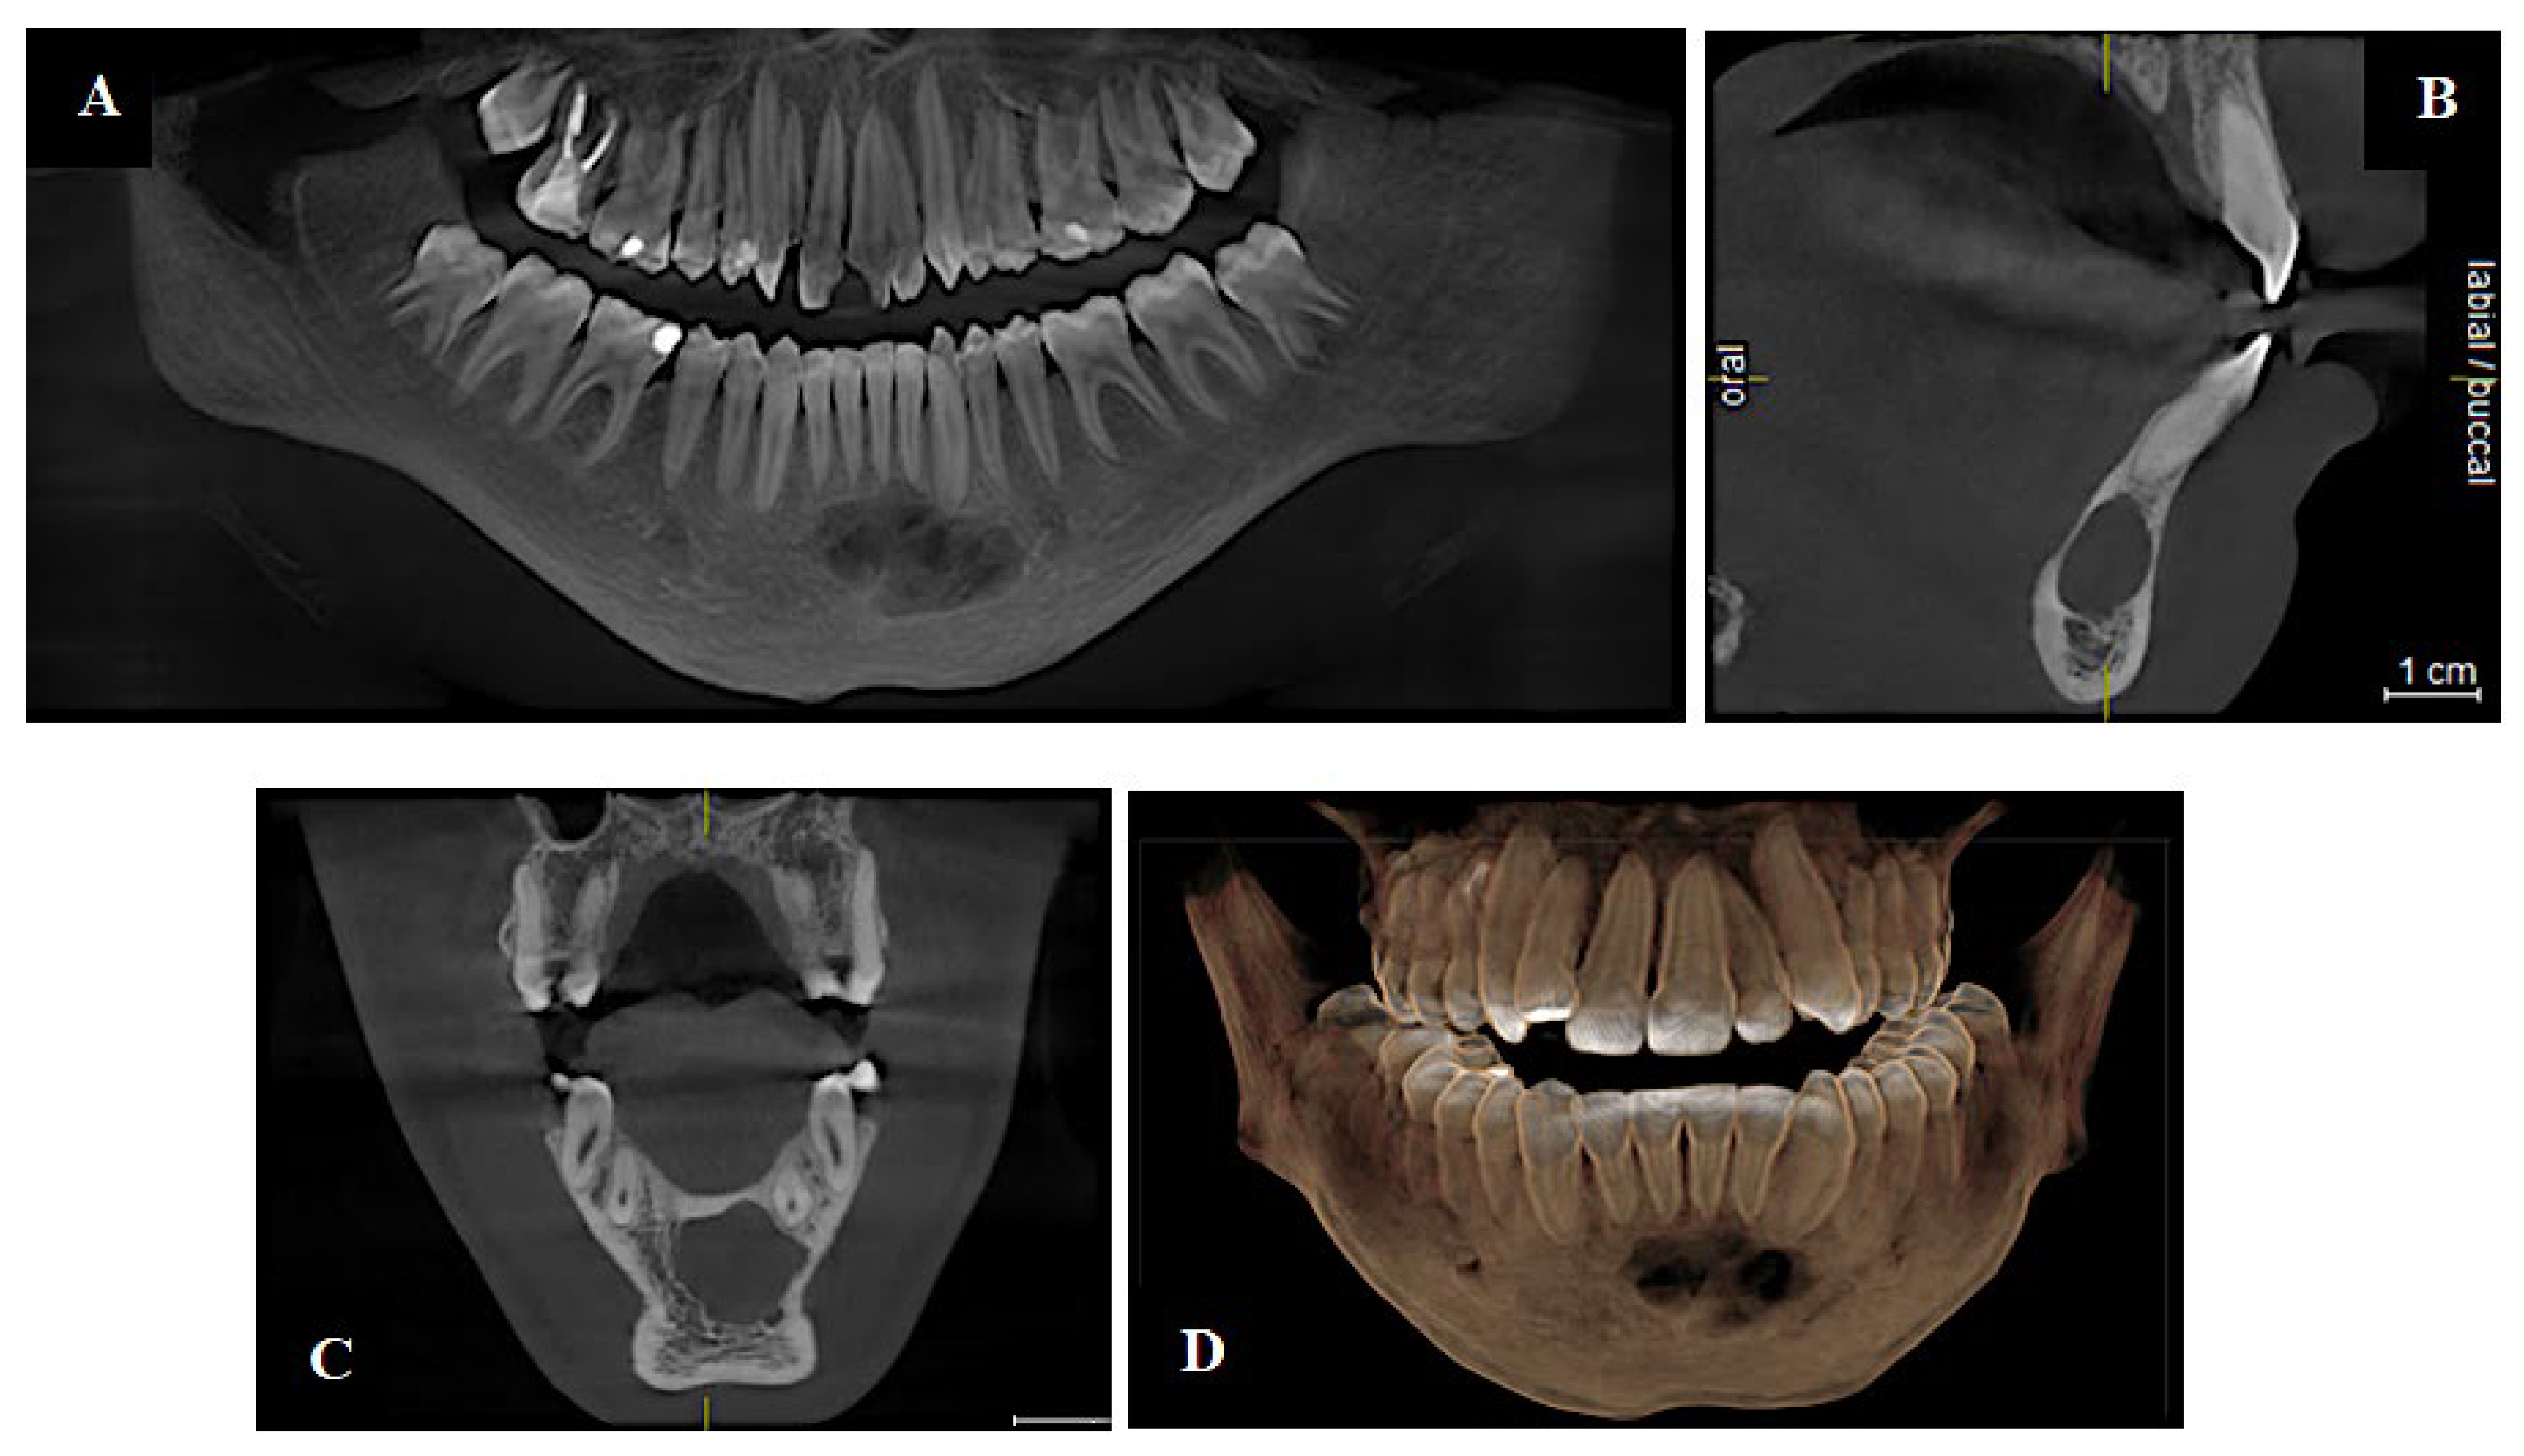

4.2. CBCT: A Foundation for 3D Visualization

5.2.2. Implantology

5.2.3. Orthodontics

- Wang, J.; Wang, B.; Liu, Y.Y.; Luo, Y.; Wu, Y.; Xiang, L.; Yang, X.; Qu, Y.; Tian, T.; Man, Y. Recent Advances in Digital Technology in Implant Dentistry. J. Dent. Res. 2024, 103, 787–799. [Google Scholar] [CrossRef]

- Bianchi, J.; Mendonca, G.; Gillot, M.; Oh, H.; Park, J.; Turkestani, N.A.; Gurgel, M.; Cevidanes, L. Three-Dimensional Digital Applications for Implant Space Planning in Orthodontics: A Narrative Review. J. World Fed. Orthod. 2022, 11, 207–215. [Google Scholar] [CrossRef] [PubMed]

- Polizzi, A.; Serra, S.; Leonardi, R. Use of CBCT in Orthodontics: A Scoping Review. J. Clin. Med. 2024, 13, 6941. [Google Scholar] [CrossRef]